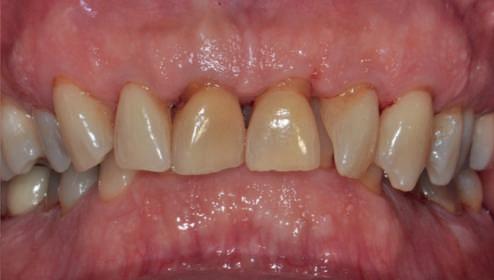

Pe parcursul ședințelor de întreținere parodontală ulterioare, valoarea PRS pentru dintele nr. 16 a fost redus la un scor de 5, un prognostic „bun”, cu o probabilitate de 93% de a-și păstra dinții din punct de vedere parodontal după 15 ani și o probabilitate de 80% de a obține acest lucru după 30 de ani. Scorul de implicare a furcației s-a redus, iar furcația vestibulară a dintelui nr. 16 a devenit improbabilă (scor = 1). Scorul de mobilitate a dintelui nr. 16 a fost redus cu 1 (scor = 1).

inferiori stângi nr. 37 și 38, pe care a decis să îi retrateze prin terapie parodontală asistată de laser. Acest retratament a reușit să elimine simptomele și a condus la stabilitate parodontală (fig. 10-13).

10, 11, 12. Imagini clinice la 4 ani după tratament: lateral dreapta (fig. 10), frontal (fig. 11) și lateral stânga (fig. 12). A existat o reducere semnificativă a PD, BOP și a mobilității.

13. Rx periapicale la 4 ani după tratament. Se observă absența pierderii osoase progresive în comparație cu fig. 7, adică, fără semne de boală parodontală activă.